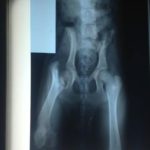

Clementine developed a limp when she was about 5 months old. . It got worse, and x-rays showed severe damage to her right femoral head. The bone appeared to literally be disintegrating. She was diagnosed with a condition called Legg-Perthes disease. Cause is unknown, but believed to be genetic. Due to its rapid onset and severity, the head of the femur had to be removed in a procedure called a Femoral Head Ostectomy (FHO). The surgery was performed June 15th, and was successful, and Clementine is now completely recovered. Her other hip is normal and she should have no future issues with it.